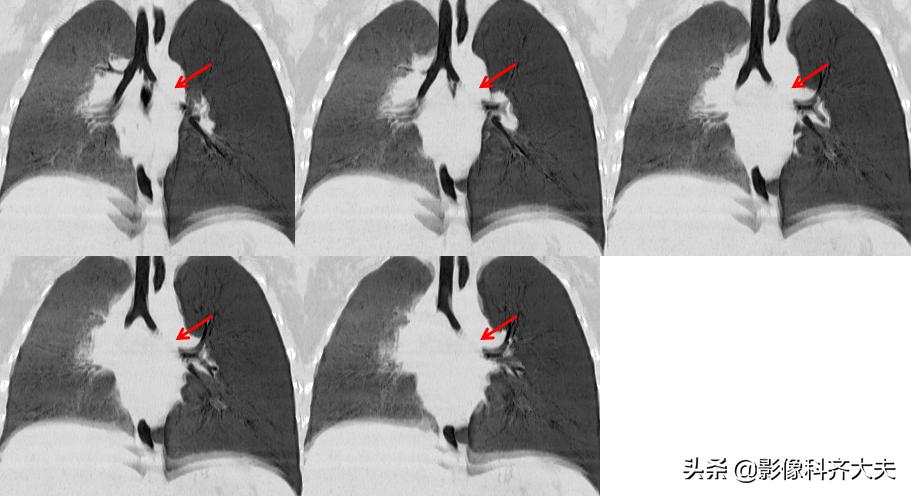

病例3、病史:患儿,两岁半。咳嗽近一个月,外院按支气管炎治疗半个月无好转。询问家属是否有吃东西呛咳病史,家属回忆一个月前还在好像吃过花生,瓜子,但不能完全确定。

图像显示在气管分叉的位置有一“瓜子”形异物的存在,尤其是冠状位显示更明显。